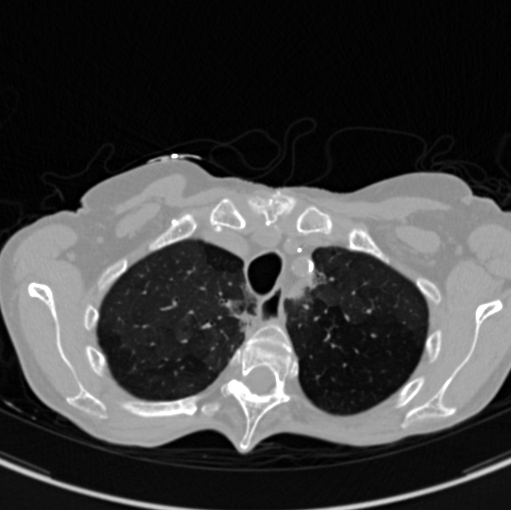

COVID-CTPRED is a comprehensive cohort database gathering an enhanced and

comprehensive chest-CT imaging together with biological,patient history, risks factors, and current clinical data.

Computational medical imaging alone has shown its ability to predict a therapeutic response

or a particular evolution after extracting from the volume of images informations that are

not visually perceptible during standard radiological reading, making it possible to construct

a radiomic signature and/or using anatomical/functional metrics.